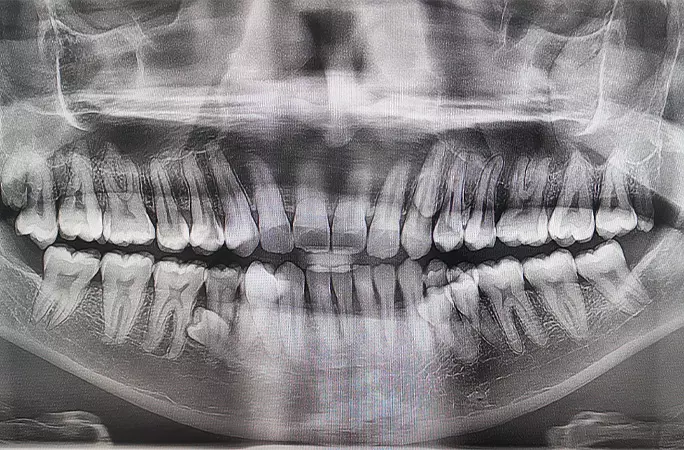

11ÀÏ ±â³×½º ¼¼°è±â·Ï¿¡ µû¸£¸é, ¸»·¹ÀÌ½Ã¾Æ ³²¼º ÇÁ¶óž ¹«´Ï¾Èµð(33)´Â ÃÖ±Ù ¡®ÃÖ´Ù Ä¡¾Æ º¸À¯ ³²¼º¡¯ ºÎ¹®¿¡ À̸§À» ¿Ã·È´Ù. ±×ÀÇ Ä¡¾Æ °³¼ö´Â ÃÑ 42°³·Î, ÀÏ¹Ý ¼ºÀÎ Ä¡¾Æ °³¼ö(32°³)º¸´Ù 10°³ ´õ ¸¹´Ù.

¾Õ¼ ÇÁ¶óžÀº µÎ ¸íÀÇ Ä¡°úÀÇ»çÀÇ °ËÁøÀ» ÅëÇØ Ä¡¾Æ °³¼ö¸¦ È®ÀÎÇß´Ù. °Ë»ç °á°ú, ±×´Â 42°³ Ä¡¾Æ ¿Ü¿¡µµ ÀÕ¸ö ¼Ó¿¡ ¸Åº¹ÇÑ Ä¡¾Æ°¡ 2°³ ´õ ÀÖ´Â °ÍÀ¸·Î ³ªÅ¸³µ´Ù.

ÇÁ¶óžÀº ¡°5³â Àü Â÷¸¦ ¸¶½Ã´Ù°¡ °¡Á·µé¿¡°Ô ¡®Ä¡¾Æ°¡ ´õ ÀÚ¶ó´Â °Í °°´Ù¡¯°í À̾߱âÇß´Ù¡±¸ç ¡°±×¶§ ³²µéº¸´Ù Ä¡¾Æ°¡ ´õ ¸¹´Ù´Â °ÍÀ» óÀ½ ¹ß°ßÇß´Ù¡±°í ¸»Çß´Ù. ±×·¯¸é¼ ¡°´ç½Ã Ä¡¾Æ¸¦ ¼¼¾îº¸´Ï 38°³¿´°í, 2023³â ÃÊ¿¡´Â ÃÑ 42°³ÀÇ Ä¡¾Æ°¡ ³ °É ¾Ë°Ô µÆ´Ù¡±°í Çß´Ù.